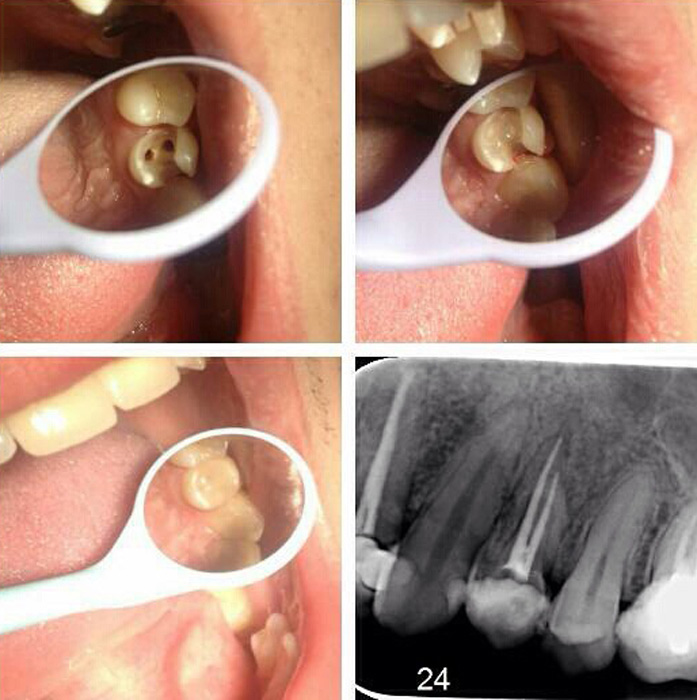

Upotreba savremenih nanohibridnih kompozita renomiranih svetskih proizvođača omugućuje izradu plombi vrhuskog kvaltiteta i estetike.

Rekonstrukcijom zuba po boji, obliku i veličini plombe izgledaju potpuno prirodno i traju dugi niz godina.